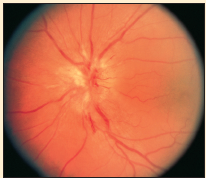

Apert Syndrome

04/29/2011

Bhagwan Das Bang, MD

<div id="article-content-body"> <p><img alt="Apert Syndrome" src="/sites/default/files/transfer/0504cfpPCApertA_thumb.jpg" style="height:73px; margin:5px;...